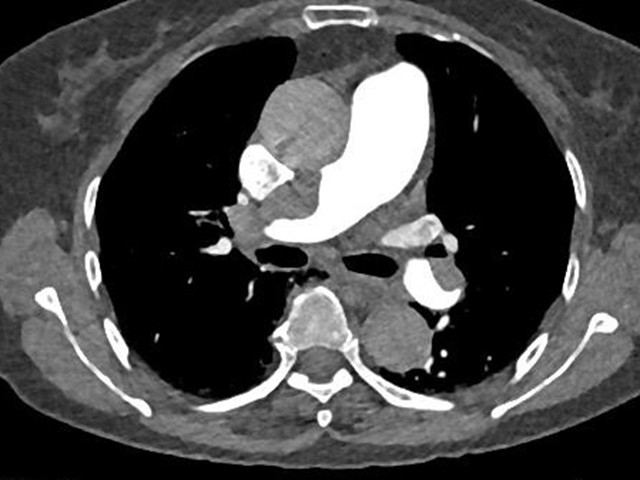

术后检查

这个真实案例强调了胸痛的凶险性、致命性以及一站式CT检查在及时诊断和治疗方面的不可或缺性。

“一站式”CT检查

胸痛三联征“一站式”CT检查是指通过一次扫描、一次注射造影剂可同时显示冠状动脉、肺动脉及主动脉三种血管的图像,有助于早期、快速诊断,同时可以最大程度降低辐射剂量。因此已成为目前评估急性胸痛患者的首选检查方法。